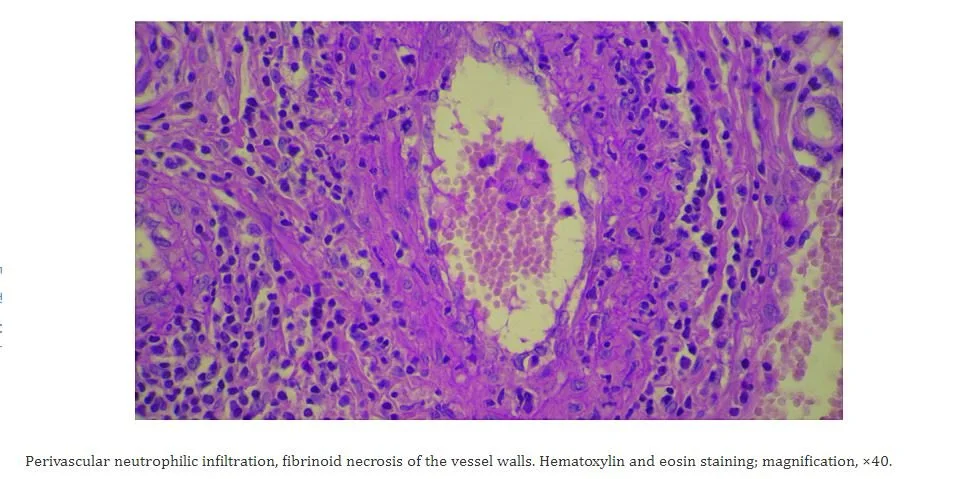

Our patient had leukocytoclastic vasculitis.  This is a small vessel vasculitis  mediated by immune complexes in the dermal capillaries and venules. These complexes  recruit neutrophils by attaching to the Fcy receptors on neutrophils.  The neutrophils then attach to vessel walls and  cause necrosis (caused by lysosomal enzymes and free radicals) allowing the neutrophils to move into the surrounding tissue.

biopsy is diagnostic for leukocytoclastic vasculitis.